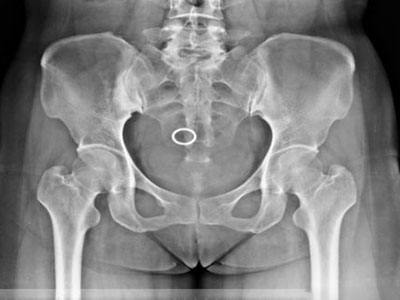

臨床表現(xiàn):癥狀多輕微,局部可有輕壓痛或肌肉痙攣。X線和CT上,髂骨耳狀面下均勻性高密度硬化,骨結(jié)構(gòu)不清,骨小梁間隙消失,內(nèi)緣以骶髂關(guān)節(jié)。骨質(zhì)硬化區(qū)表現(xiàn)為三角形、新月形或梨形,尖端向上,寬基向下。病變范圍不一,可累及耳狀面的全部或中下2/3,亦可僅限于中1/3或下1/3。椎體也可發(fā)病,多位于腰椎前上角,以L4、L5多見,多單發(fā),亦可累及多個椎體,表現(xiàn)位椎體前上緣三角形致密影,椎間縫正常。部分病例經(jīng)隨訪觀察病變范圍可縮小,骨硬化密度減低,但多數(shù)無任何改變。

常見的致密性骨炎:骶髂關(guān)節(jié)致密性骨炎

骶髂關(guān)節(jié)致密性骨炎臨床癥狀是患有復(fù)發(fā)性腰痛,有時可向下放射至臀部和大腿,但不是根性疼痛,腰活動時可加重癥狀,與妊娠、勞損及病灶性炎癥有關(guān)。

臨床表現(xiàn):患者平素身體健康,其主訴為腰腿痛。疼痛一般較輕,也有無癥狀或疼痛較重者。疼痛為慢性、間歇性酸痛,并可隨妊娠或生產(chǎn)次數(shù)的增加而加重。多數(shù)病例病變發(fā)生于下腰、骶部,疼痛可以放射到臀部和大腿后部,呈非神經(jīng)根樣疼痛。這種疼痛在白天和夜間都可能持續(xù)存在,有時較為嚴(yán)重,沒有明顯的晨起僵硬感�;颊咭话銢]有全身癥狀(如:體重下降、乏力和發(fā)熱),沒有外周關(guān)節(jié)腫痛、肌腱端炎等。